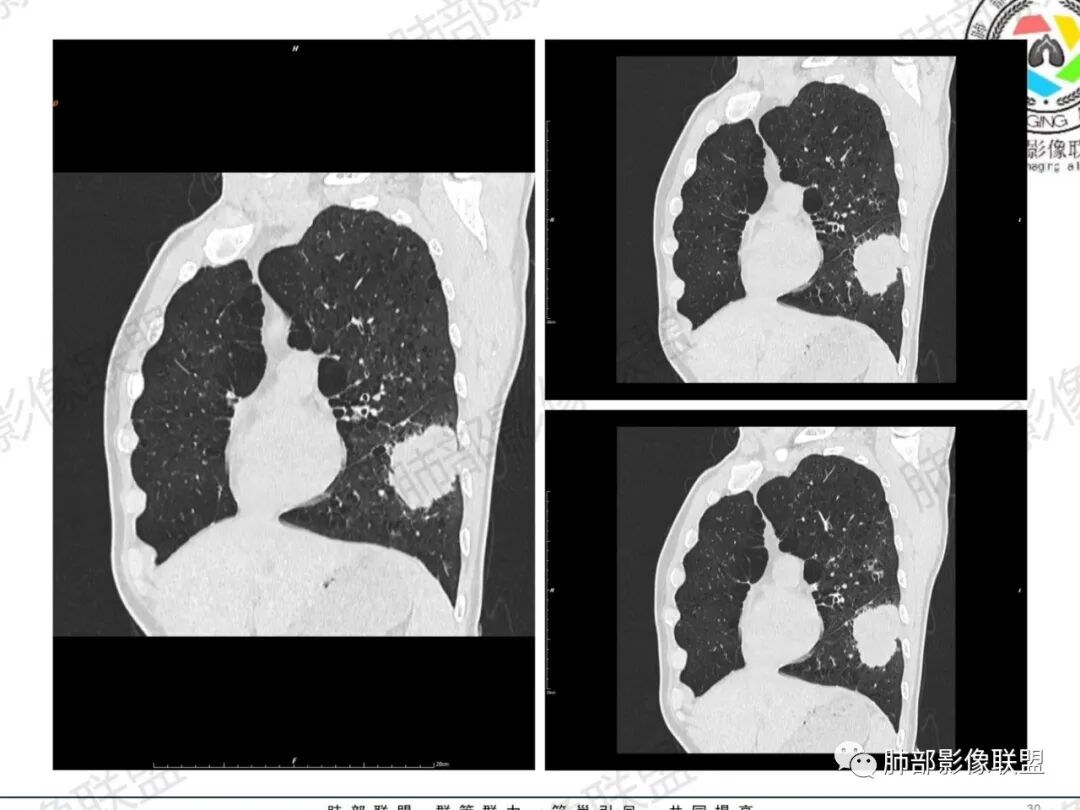

一切∮随缘:左肺下叶不规则肿块,边缘光滑,平直,局部彭隆,分叶,近端支气管堵塞,远端与胸膜相贴,平扫密度尚均匀,增强后不均匀强化,内部可见低密度坏死,胸膜下多发肺气肿,伴双肺散在光滑小结节,实验室肿瘤标志物高,考虑恶性:神经内分泌癌(大细胞),腺癌,鳞癌。

琦遇:恶性没有问题,肺气肿底子、病灶分叶、少许毛刺、叶间胸膜凹陷、部分边缘可见清晰的GGO、胸膜牵拉凹陷、局部胸水、近端支气管截断、部分支气管被推移、占位效应明显、强化特点为不均匀强化、内部有少许沼泽样低强化区,强化部分轻中强化为主、余肺可见转移性结节、左肺上叶似为囊腔型腺癌一枚,肿瘤标志物提示非小、神经内分泌,综合分析考虑大神泌、腺癌、腺鳞癌、鳞癌  同时左肺上叶囊腔型腺癌  肺转移

飞鹰行动:中年人,男性,胸疼入院,左肺下叶占位,张力较高,边界可见分叶,局部可见明显收缩性改变,增强病灶内部有延迟强化表现,考虑恶性病变,大细胞癌伴肺内转移或者囊腔样腺癌伴转移。

蕊:中老年男性,吸烟史,肺气肿背景,左肺上叶类圆形肿块影,边界清晰,边缘凹凸不平,有分叶,支气管进入阻断,临近胸膜栽赃,整体病灶膨隆,局部周围可以清晰ggo,临近叶间裂内凹,轻度强化,并可见多个低密度区,坏死可能,界线不清;肺内多结节,边缘光滑,考虑恶性伴转移,鳞癌、腺癌

傅昌瑜:中老年男性,肺气肿背景,右胸背疼痛1周。CEA、NSE、CYFRA—211升高。左上肺混合磨玻璃结节,内见较多空泡和扩张支气管。左下肺胸膜下肿块,边缘较光滑,深分叶,似有血管进入,与支气管关系不清,内见不均匀强化,见沼泽地样坏死,有胸膜栽赃。另两肺多发圆形小结节。考虑恶性并肺内转移,多原发可能性大,左上肺腺癌,左下肺病理难以判断,小细胞癌?鳞癌?

小锁:中老年男性,肺气肿背景,右胸背疼痛1周。CEA、NSE、CYFRA—211升高。左上肺混合磨玻璃结节,边界清楚,内见较多空泡。左下肺肿块,边缘清楚,深分叶,有血管和支气管进入,胸膜凹陷。另两肺多发圆形小结节。考虑双发原位癌,左上肺腺癌,左下肺大神泌或腺鳞癌可能,肺内转移。

蓝天白云:中年男性,肺气肿背景,左肺下叶肿块,边缘膨隆,有分叶,内有湖泊样坏死,有轻中度强化,局部胸膜栽赃,收缩力不强,周围见肺气肿征象。左肺上叶混合磨玻璃影,边界清楚,考虑都是恶性,左上肺iac,左下肺腺鳞癌,或大细胞肺癌可能。两肺多发结节,考虑转移

LCNEC最常见的影像特征包括:(1)肿块发生部位:周围型肺癌为主,少数发生于肺中央。(2)肿块大小及形态。因肿瘤细胞生长迅速常形成较大肿块,因此其体积一般较大,直径常在3~10cm范围内,病灶常为不规则形软组织肿块。(3)肿块边界。多数学者报道大多数肿块边界清晰,边缘呈分叶状,毛刺征及“胸膜凹陷征”少见,认为与该病对周围组织浸润较轻及较少产生纤维瘢痕组织牵拉有关联。(4)肿块密度、强化特点及代谢情况。据文献报道,该类肿瘤因体积较大CT上常见软组织肿块,且多数密度不均匀,内见囊变坏死区,增强后呈轻或中度不均匀强化(可见强化者占75.7%),认为其强化特点与其内部肉眼可见坏死灶和肿瘤较大直径有关。(5)伴随症状及远处转移。该病恶性程度高,侵袭性强,常侵犯邻近结构,如胸膜、心包、邻近骨质或纵隔内组织等,易出现纵隔淋巴结转移,部分发生肺内及远处转移,少数早期可出现广泛远处转移。